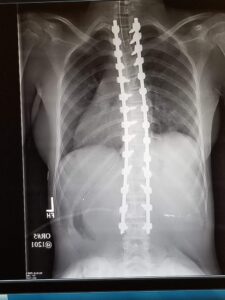

In June 2018, I was diagnosed with 60-degree scoliosis. The curvature threatened my heart and lungs. I wore a brace to slow its progression, but the curve worsened, making surgery unavoidable.

Despite the emotional weight, I faced spinal fusion surgery with determination. Surgeons placed 28 screws and two rods in my back. It was life-altering, but it gave me stability and protected my heart and lungs. I’m so grateful for Dr. John Ashgar and the amazing work he did.